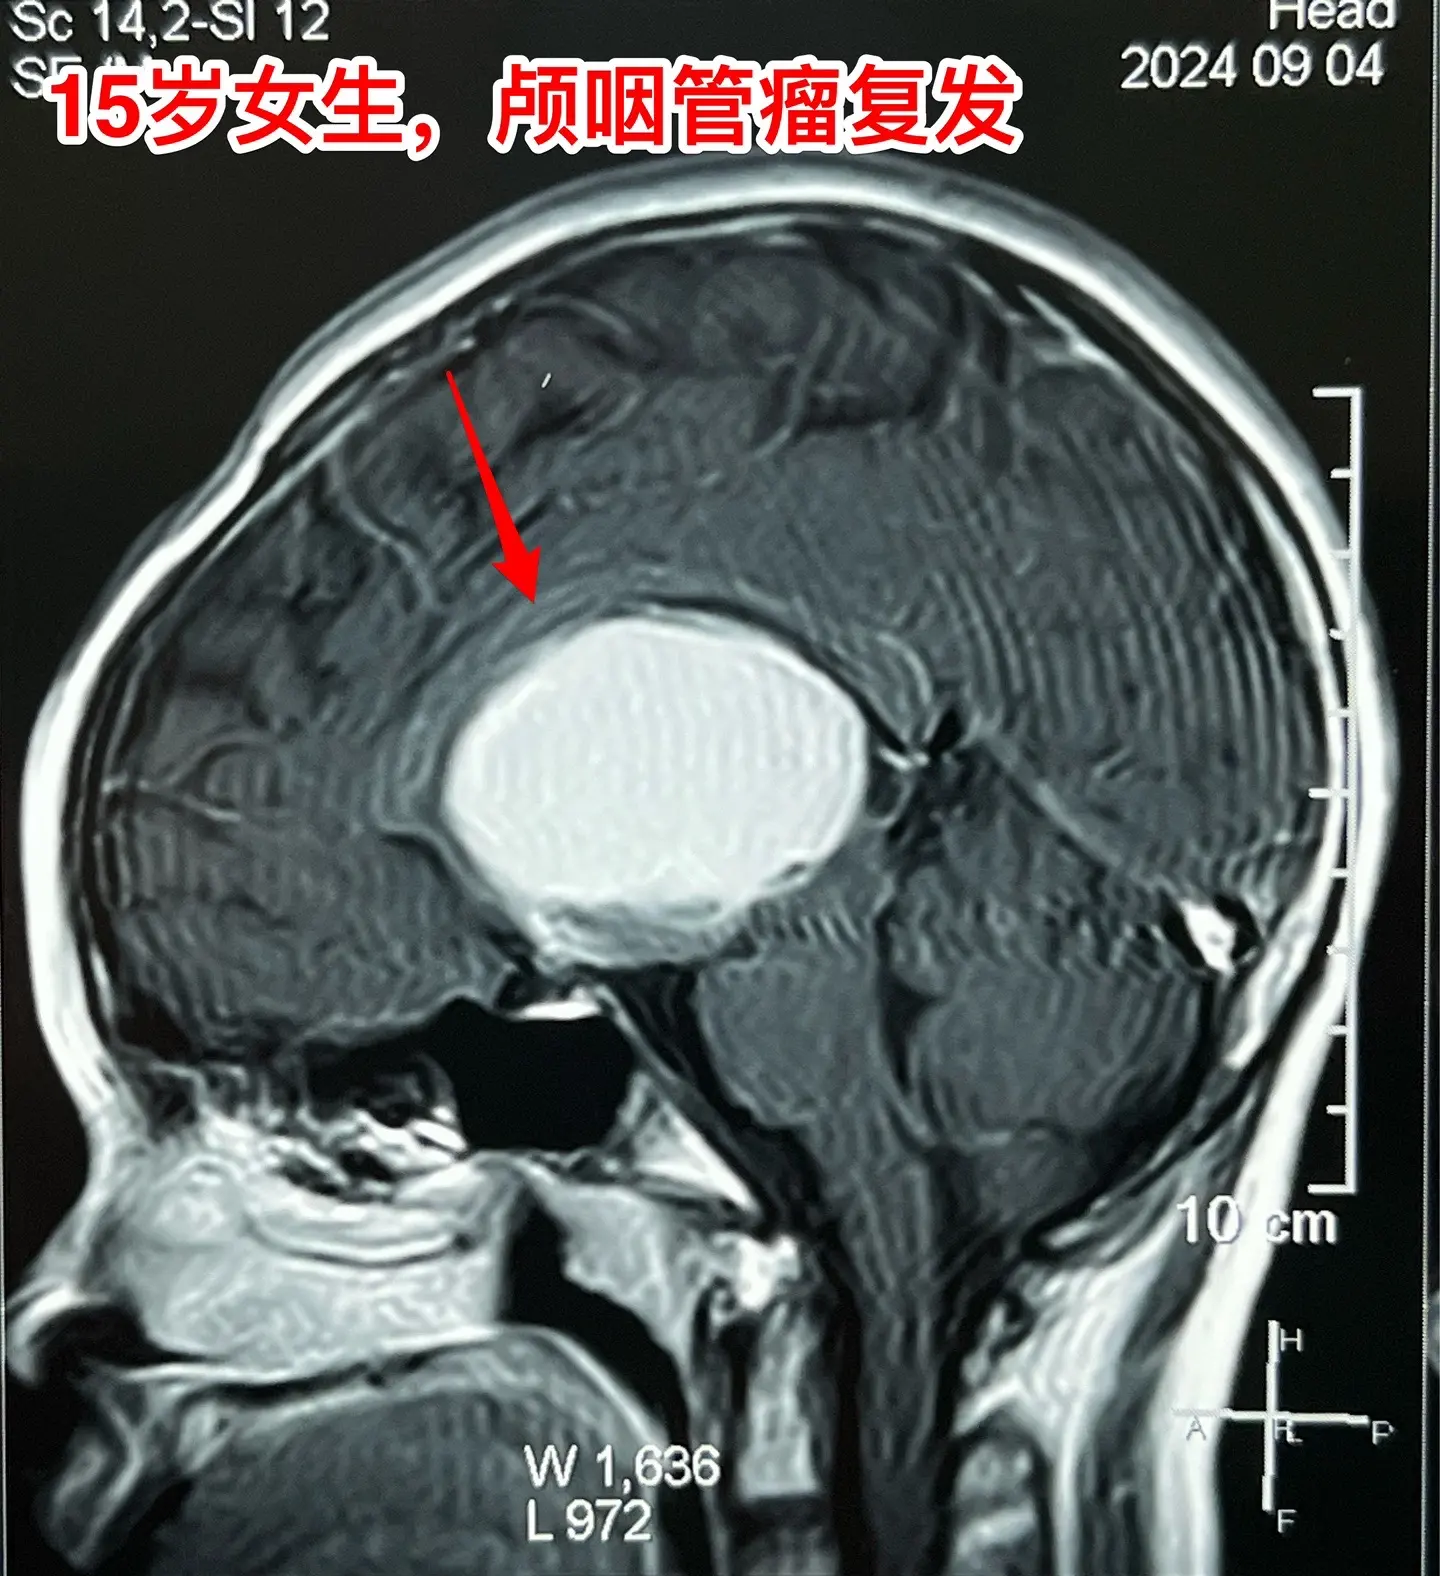

颅咽管瘤不是按匀速生长,进展很难预料。15岁的福建龙岩市女生,因颅咽管瘤之前在上海作过一次开颅手术,只有左眼有有效视力。两年前就发现肿瘤复发了,多次复查磁共振,显示肿瘤生长速度缓慢。2023.8复查磁共振见图,无明显症状,家长主张继续观察。今年八月患者出现症状,复查磁共振显示肿瘤体积显著增大,见图。所以说,颅咽管瘤的生长速度不是匀速的,医生也无法预测疾病的进展情况。

9月11日作了手术,经纵裂入路顺利切除肿瘤。经过仔细对比之前的磁共振,找到了复发肿瘤的起源点,才确定了这个手术入路。手术后患者语言、运动能力均好。发热持续时间比较长,经用抗菌药治疗后平稳了,十一前出院了。